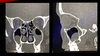

Estudio de imagen que se solicita para sinusitis

Tomografía de nariz y senos paranasales

*Gold standard

En que px se indica la TC para sinusitis

Oncológicos, inmunosuprimidos y sinusitis crónica